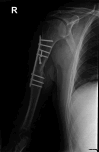

An Upper-Arm Clostridium perfringens Fracture-Related Infection: A Case Report

Fracture-related infections (FRI) pose serious complications, requiring swift surgical intervention. Although C. perfringens infections in FRIs are rare and literature is scarce, this case highlights the successful management and good functional outcome, offering valuable insights for clinicians dealing with such infections.